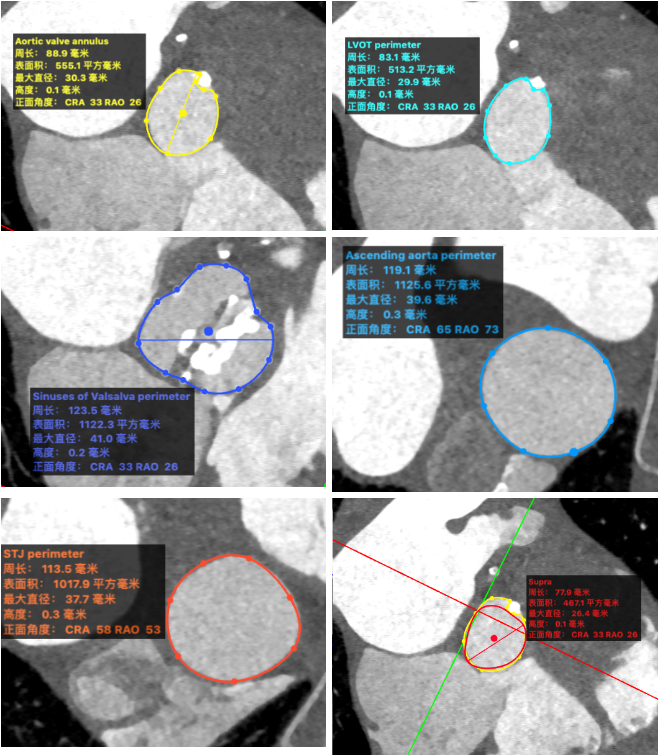

CT分析结果:

图示:瓣环、左室流出道、主动脉窦、升主动脉、窦管结合及瓣上结构部大小。